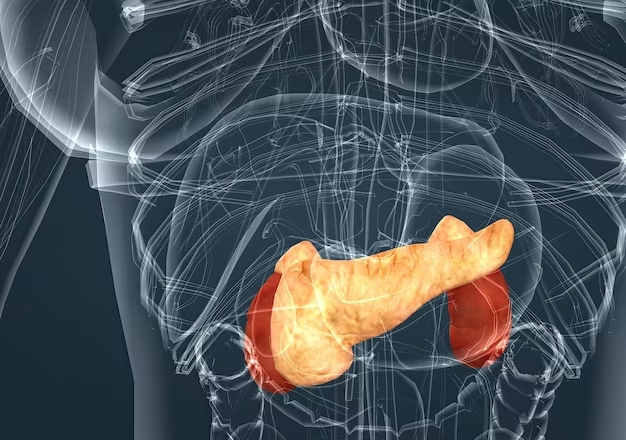

La curvatura posterior del páncreas, que se ajusta a la forma de la columna lumbar en el área correspondiente a las vértebras L1 a L2, es una característica anatómica que presenta un propósito fundamental en el contexto del cuerpo humano.

La disposición anatómica del páncreas, con esta concavidad posterior, tiene sus raíces en su ubicación en el abdomen. Este órgano vital se encuentra situado detrás del estómago y en proximidad a la columna vertebral. La adaptación de su forma a la curvatura lumbar se debe en parte a la necesidad de encajar dentro del espacio disponible en la cavidad abdominal. La concavidad permite que el páncreas se ajuste y acomode entre otros órganos cercanos, como el estómago y el intestino delgado.

Una de las ventajas funcionales de esta conformación es la protección que brinda al páncreas. Al moldearse sobre la columna lumbar, el órgano adquiere una especie de escudo natural contra posibles daños o traumas externos. La estructura ósea de la columna vertebral actúa como una barrera defensiva que ayuda a preservar la integridad del páncreas en esta región del abdomen.

La interacción con otros órganos también desempeña un papel importante. El páncreas comparte espacio con el duodeno, la primera porción del intestino delgado. La concavidad posterior del páncreas facilita la cercanía y la comunicación entre estos dos órganos. Esta proximidad es esencial debido a que el páncreas libera enzimas digestivas hacia el duodeno, lo que contribuye a la descomposición de los alimentos y al proceso digestivo en general.

Además, la conformación del páncreas podría estar influenciada por la distribución interna de sus tejidos funcionales. Como órgano con funciones tanto exocrinas como endocrinas, el páncreas alberga tejido que produce enzimas digestivas y tejido que secreta hormonas como la insulina. La curvatura lumbar podría ser una característica que favorece esta distribución y que facilita la liberación adecuada de enzimas y hormonas en sus respectivos lugares.